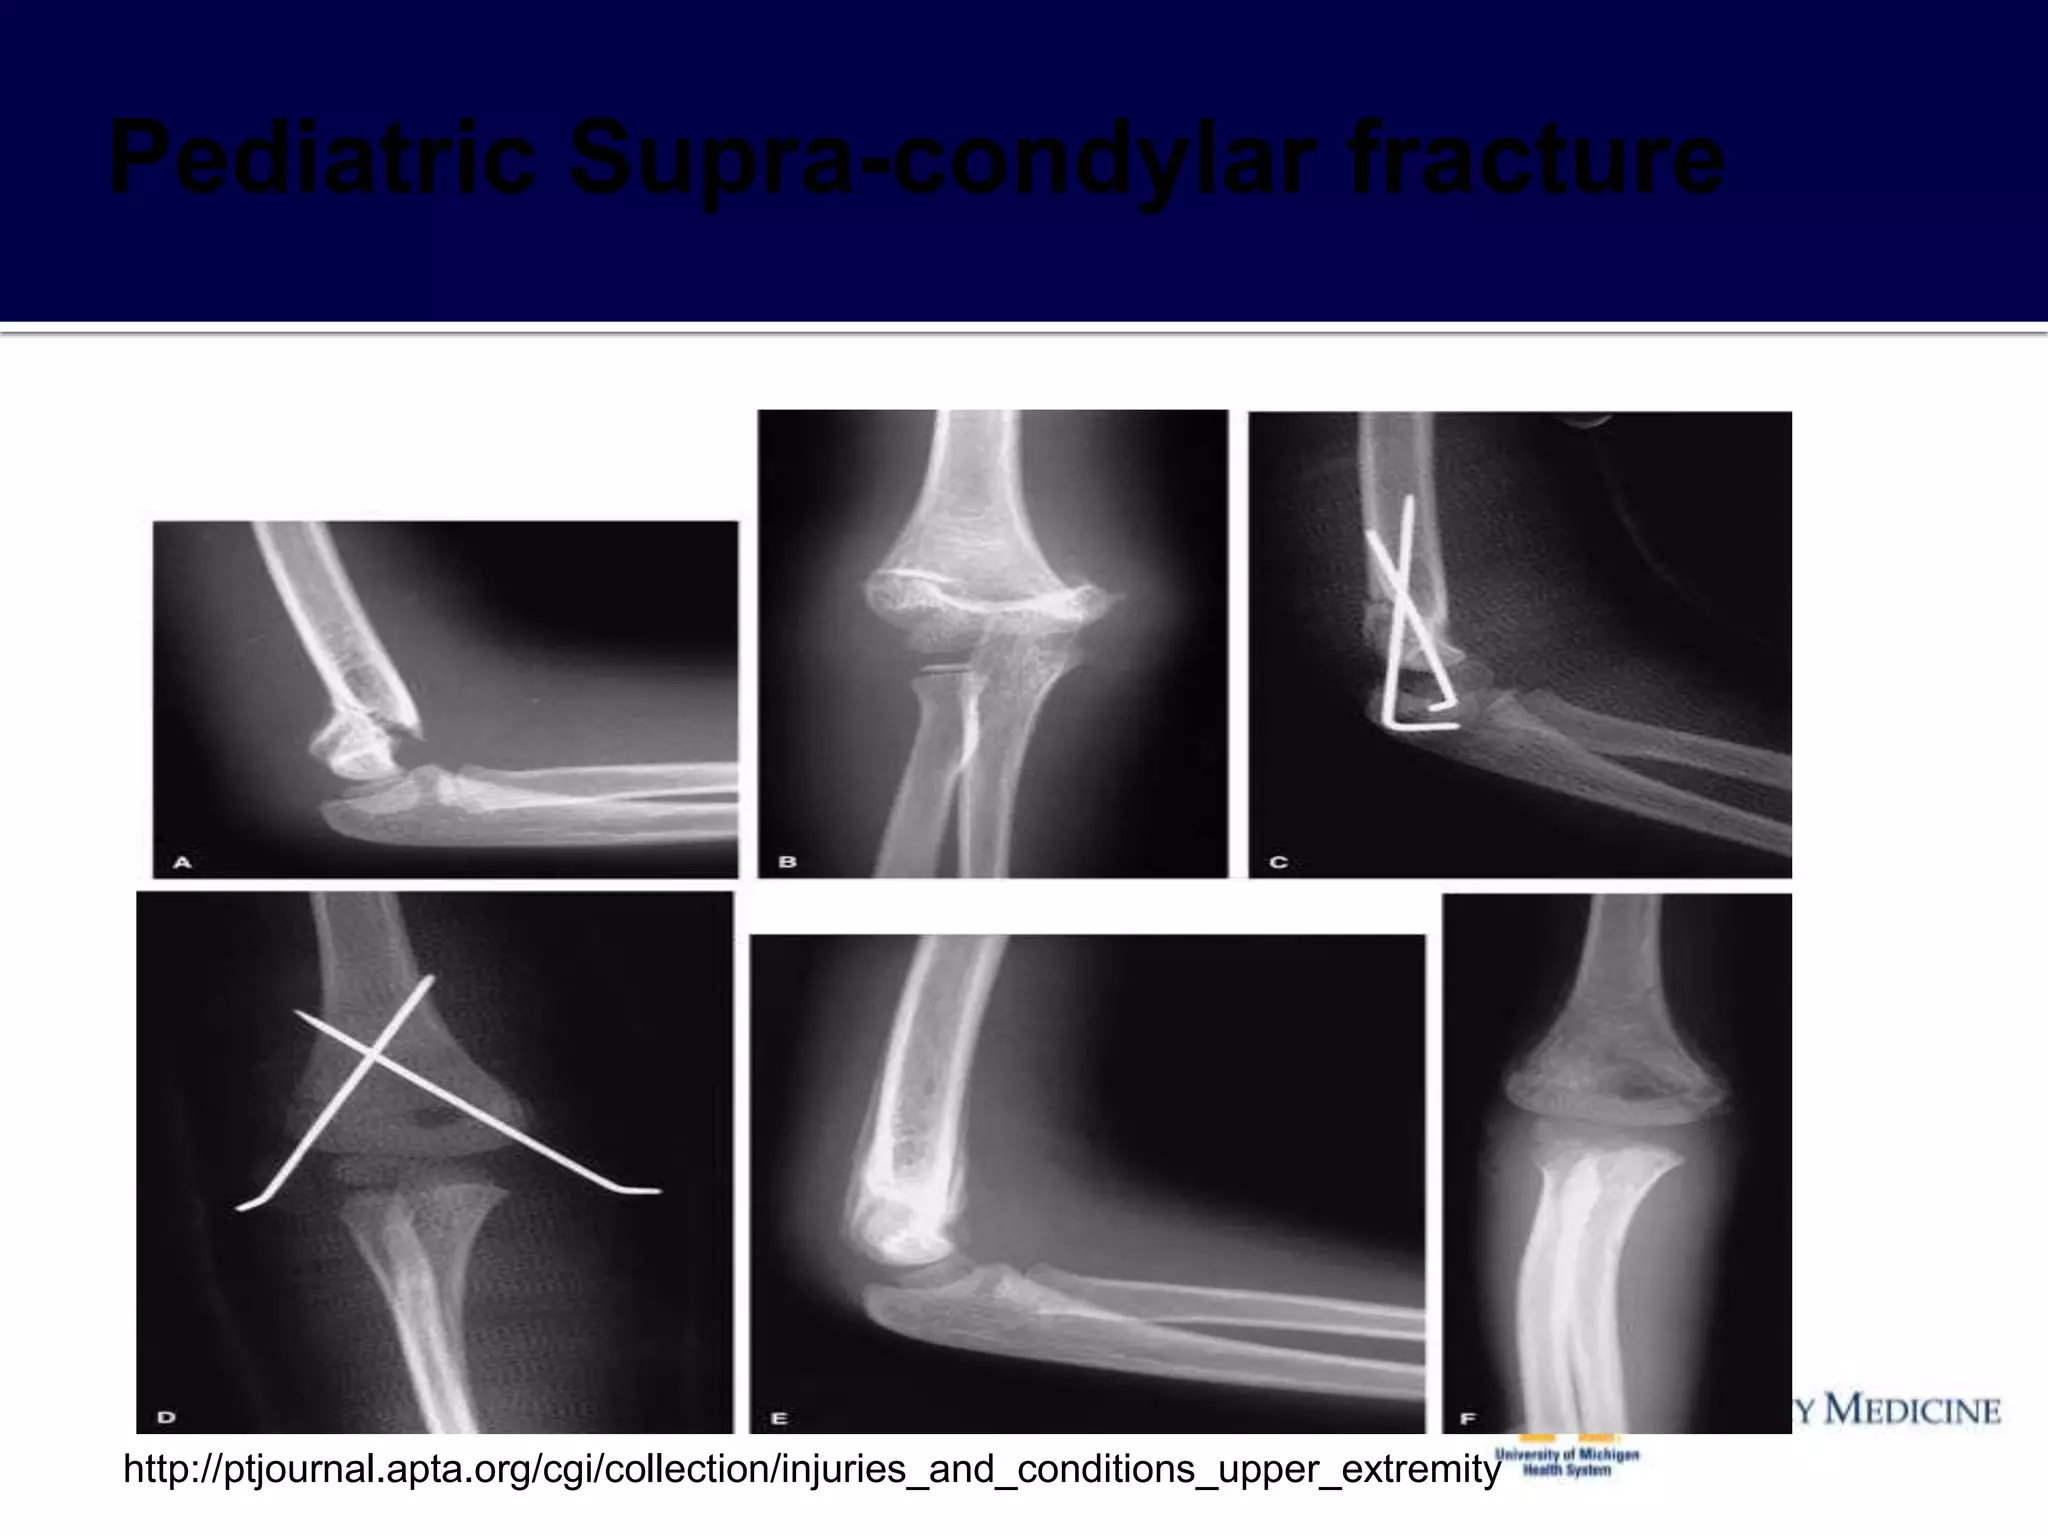

 Supracondylar Extension Fractures

 Mechanism of injury

 Imaging

▪ Sharp fracture fragments displaced anteriorly with potential for injury

 Treatment

▪ May be discharged home with close follow-up

▪ Orthopedic Consultation and reduction

admission for observation

 Absolute Emergency

possible

POP after reduction

out after reduction